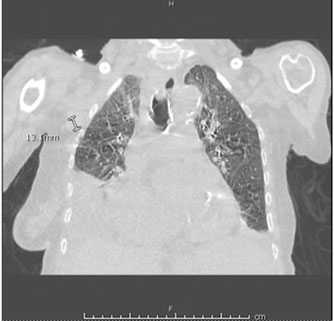

She stated that her shortness of breath was exacerbated by exertion and associated with orthopnea, paroxysmal nocturnal dyspnea, and swelling in her lower extremities. She denied any recent history of trauma, symptoms of respiratory infection, and had not had any recent surgery. After a chest X-ray was completed and demonstrated a small left and moderate right pleural effusion (Figure 1 and Figure 2), she was given a trial of furosemide. Five days later, she returned to the Cancer Center stating that her symptoms had not improved. At that time, she was noted to have a SpO2 of 85% on room air and rales in the bilateral lower lung fields. She was immediately referred to the hospital for admission.

Upon arrival in the hospital, she was afebrile, normotensive, with improved O2 saturation on nasal cannula. Her physical examination was notable for atrial fibrillation, decreased breath sounds in the right lower, left middle, and left lower lung fields with accompanying rales. Her labs revealed white blood cell (WBC) of 34.25 × 103/uL with 82% lymphocytes, hemoglobin of 11.0 g/dL, platelets of 106 × 103/uL, creatinine of 1.13 mg/dL, aspartate aminotransferase (AST) of 46.0 U/L, alanine aminotransferase (ALT) of 11.0 U/L, alkaline phosphatase 120 U/L, and pro-brain natriuretic peptide (pro-BNP) 2823 pg/mL. Computed tomography of the chest (Figure 3 and Figure 4) demonstrated large right and moderate left pleural effusions with near complete and partial atelectasis with marked axillary lymphadenopathy. She was started on diuretics for suspected pleural effusion secondary to congestive heart failure.

Figure 3: Coronal view of CT chest without intravenous (IV) contrast showing large right and moderate left pleural effusions with associated atelectasis and marked axillary lymphadenopathy.

Figure 4: Axial view of CT chest without IV contrast showing large right and moderate left pleural effusions with associated atelectasis and marked axillary lymphadenopathy.